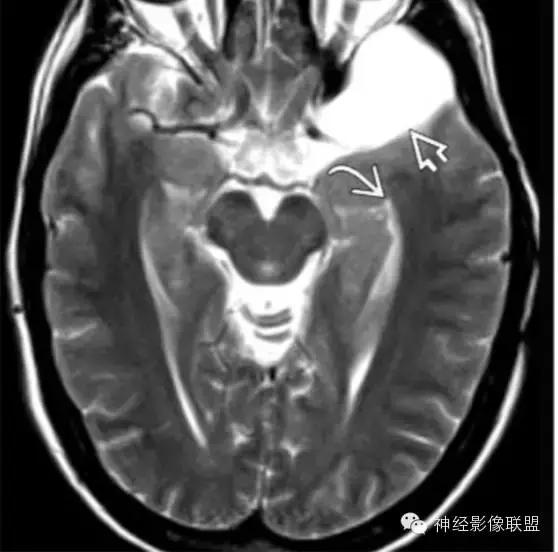

蛛网膜囊肿